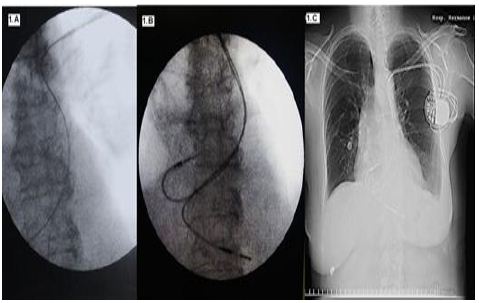

A nivel del surco deltopectoral izquierdo se realizó una incisión quirúrgica de 4 cm y se efectuó la apertura por planos sin visualizar la vena cefálica izquierda. Se procedió entonces a realizar doble punción de la vena subclavia izquierda bajo visión fluroscópica, mediante la técnica de Seldinger y con el empleo de introductores venosos 9 French. Al progresar las guías se observó que al inicio, descendían por el borde paravertebral izquierdo, para luego alcanzar la aurícula derecha en su porción baja, lo cual estaba en relación con un trayecto a través de la VCSIP que drenaba en el seno coronario. (Figura 1-A)

El electrodo bipolar de fijación pasiva (Capsure SP Novus - Medtronic) se colocó en el ápex del ventrículo derecho, con previa preformación de la guía en forma de L. Luego se avanzó un electrodo bipolar de fijación activa (CapsureFixNovus - Medtronic) hacia la aurícula derecha y mediante el empleo de una guía en forma de J se ubicó en la orejuela derecha. (Figura 1-B). Al implante, se registraron las siguientes medidas: aurícula derecha (umbral: 0.9V, amplitud de la onda P: 2,3 mV e impedancia: 446) y ventrículo derecho (umbral 0.9V amplitud de la onda R: 11,2 mV e impedancia: 571). Después fijados los electrodos, se conectaron a un generador (Medtronic ADAPTA ADDR01), y se ubicaron en un bolsillo subcutáneo. Se finalizó con el cierre por planos. La paciente se egresó 24 horas, luego del procedimiento, previa comprobación de la posición adecuada de las sondas endocavitarias y con óptimos umbrales de estimulación. (Figura 1-C)

Figura 1. A. Imagen fluroscópica donde se observa el trayecto anómalo de la guía de punción de la vena subclavia izquierda, la que desciende por el borde paravertebral izquierdo. B Ubicación final de los electrodos en la orejuela derecha y en el ápex del ventrículo derecho. C Radiografía de tórax en vista anteroposterior, tomada a las 24 horas del implante y con adecuada posición de las sondas endocavitarias.